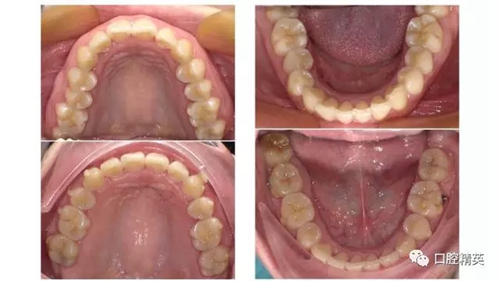

樊老師近期隱形矯正病例: